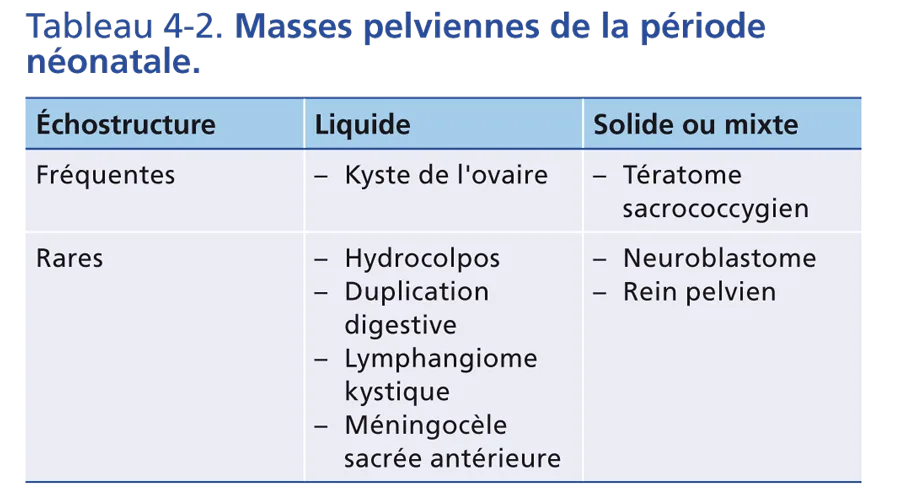

Masses pelviennes de la période néonatale

Elles sont listées selon leur échostructure dans le tableau 4-2. Elles sont très souvent dépistées actuellement par l’échographie anténatale.